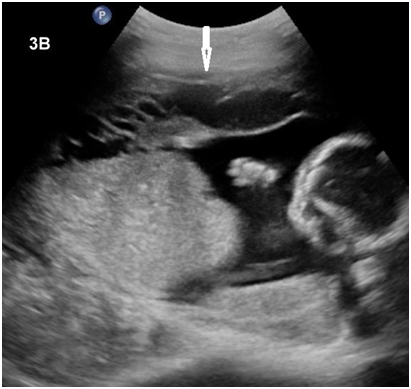

On examination, the patient’s temperature was 36.8 0C, blood pressure was 78/55mmHg, heart rate was 115 beats per minute. There were signs of acute abdomen with diffuse tenderness noted over the abdomen with guarding. On speculum examination, the cervical os was closed and there was no per vaginal bleeding. The patient was stabilized and fluid resuscitation immediately commenced. Urgent blood investigations sent off showed a full blood count with hemoglobin of 10.4g/dL and a total white cell count of 21.9 x 109/L. Urgent sonographic imaging showed an intrauterine live fetus with fetal tachycardia and irregular heart rate. There was intra-peritoneal free fluid and blood clots seen, indicative of hemoperitoneum (Figure 1). The uterine myometrium appeared discontinuous at the fundus, suggestive of uterine rupture (Figure 2). An i-STAT finger print blood count subsequently done showed a hemoglobin level of 5.8g/dL and packed red blood cell transfusion was immediately commenced. The patient was sent to the women’s intensive care unit and preparation for emergency laparotomy was initiated.

Figure 2 Trans-abdominal ultrasonography, transverse view of the uterus (12 MHz linear transducer, Philips iU22, A) and (5 MHz curved transducer, Philips iU22, B) demonstrate defect in the myometrium (arrow).